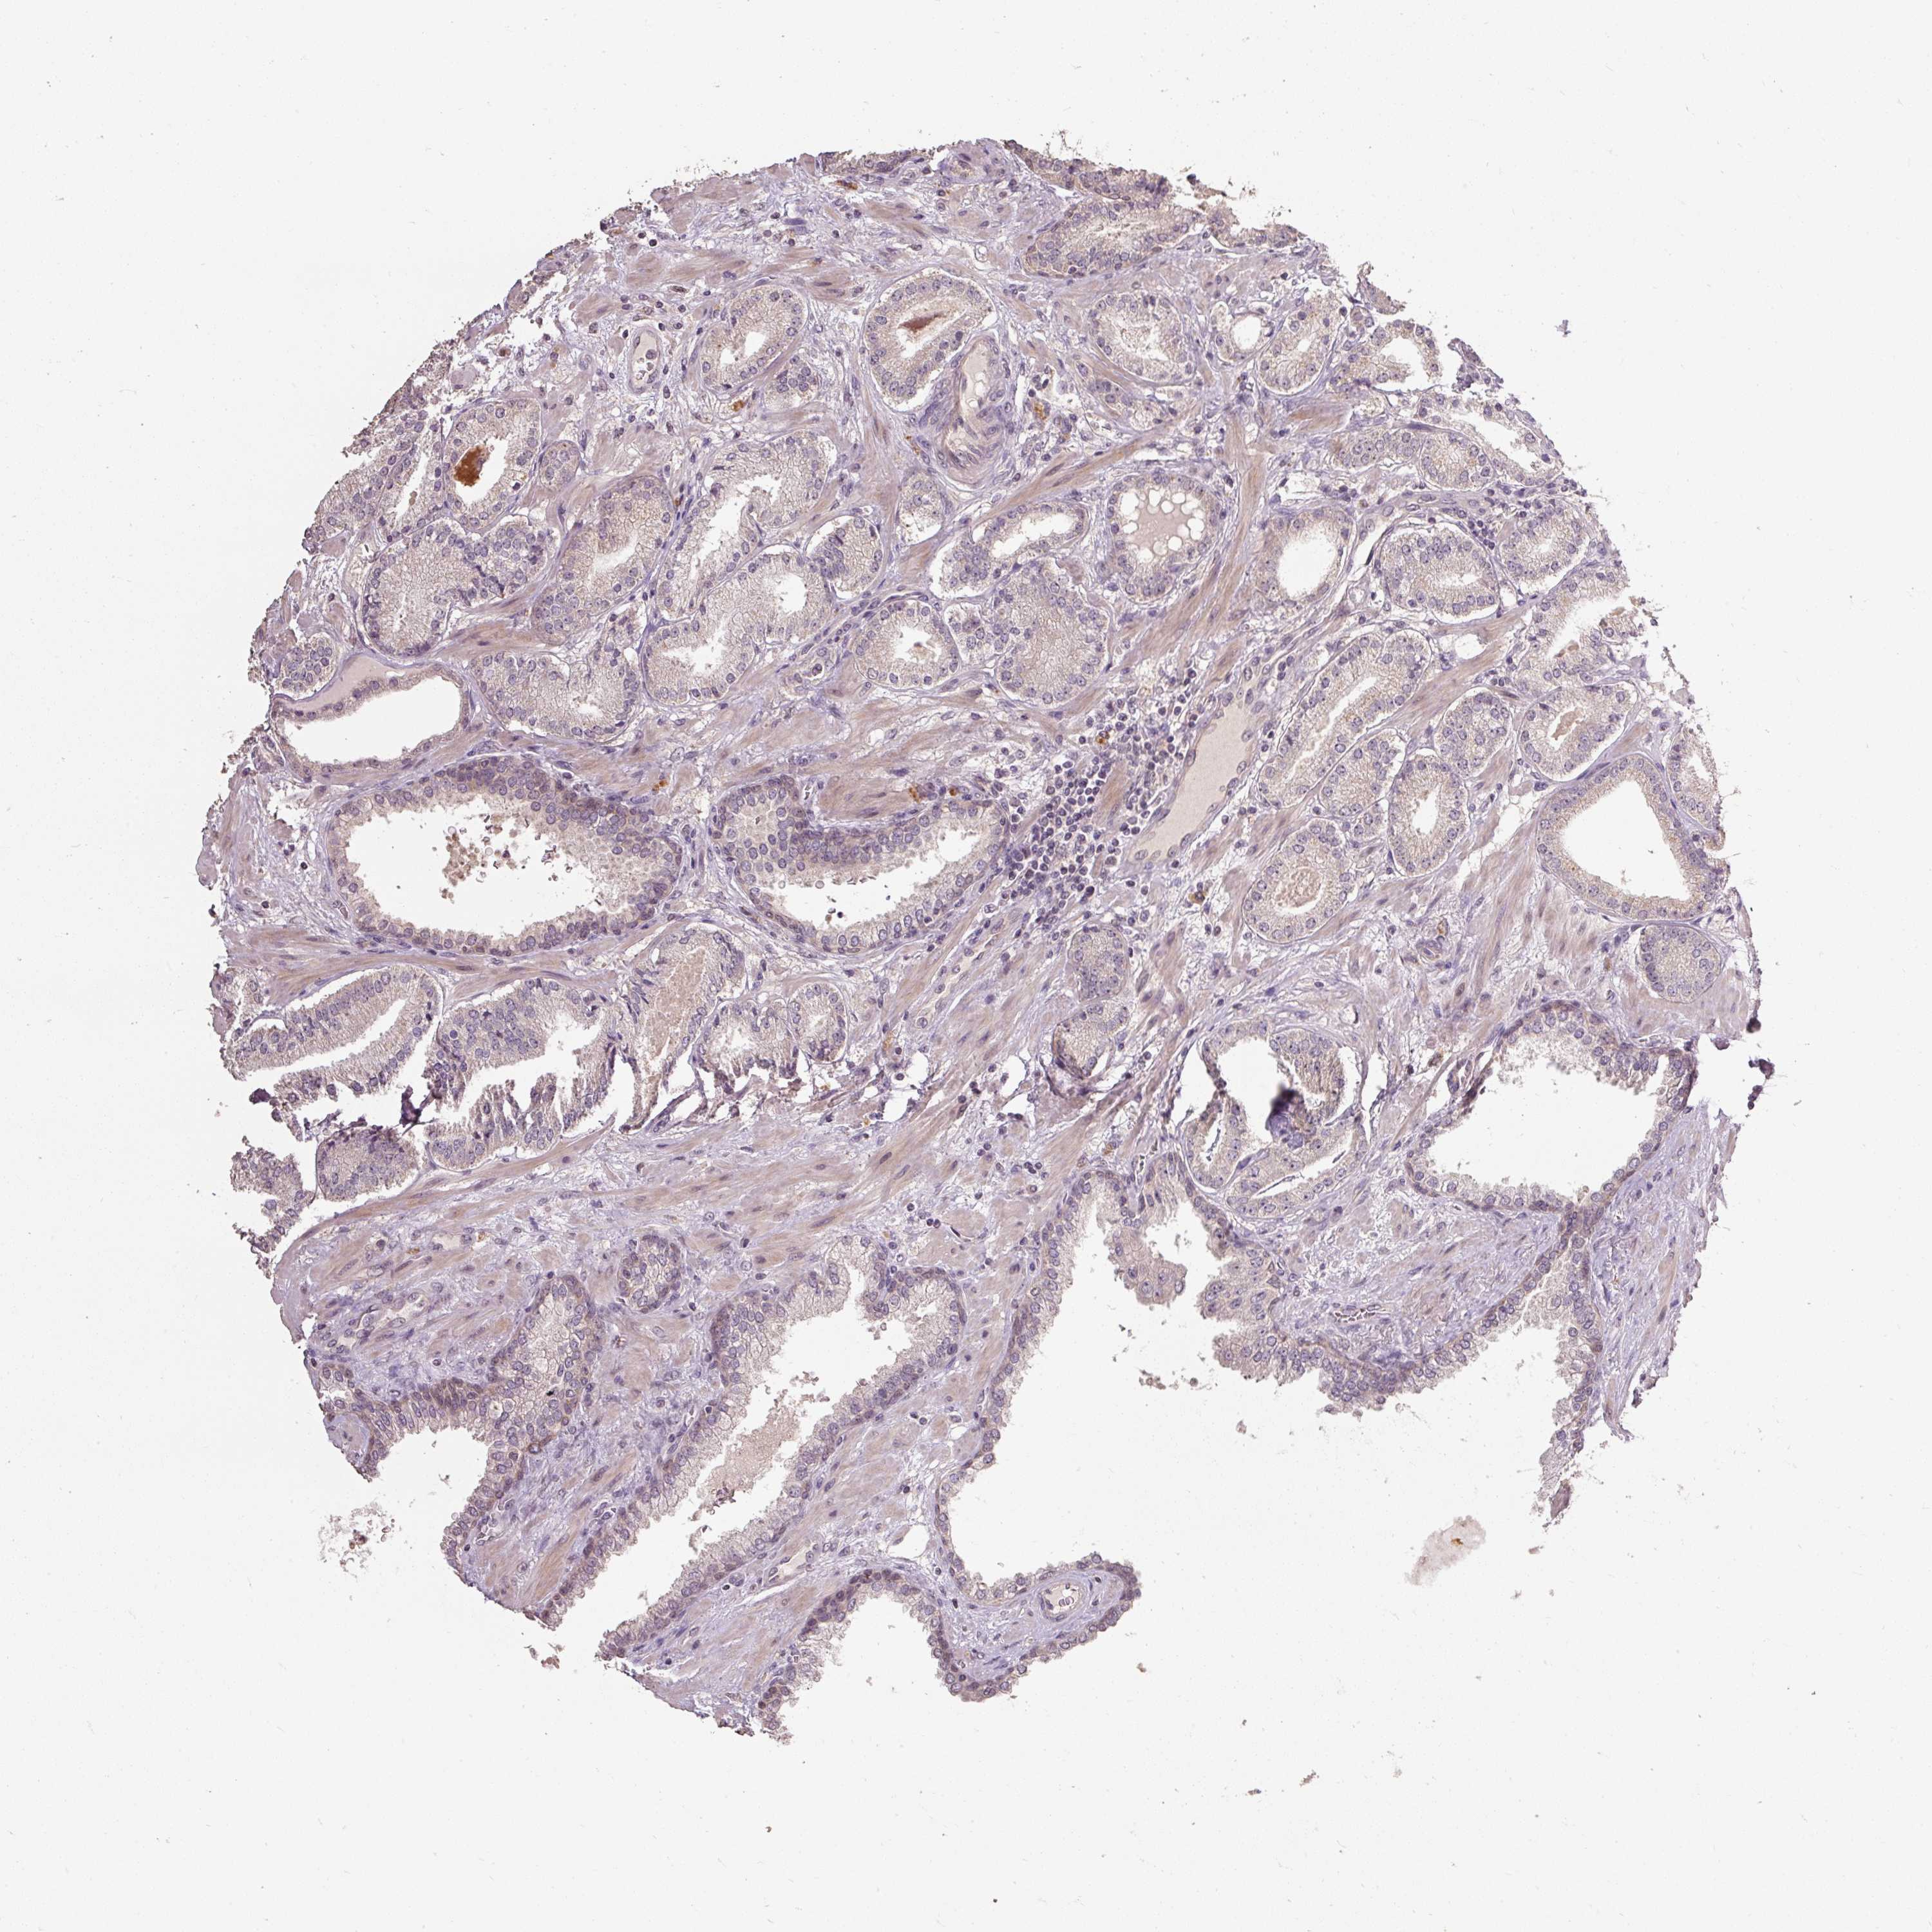

PROSTATE CANCER - Protein expressioni

A mouse-over function shows sample information and annotation data. Click on an image to view it in a full screen mode. Samples can be filtered based on level of antibody staining by selecting one or several of the following categories: high, medium, low and not detected. The assay and annotation is described here.

Note that samples used for immunohistochemistry by the Human Protein Atlas do not correspond to samples in the TCGA dataset.

Antibody stainingi

Antibody staining in the annotated cell types in the current human tissue is reported as not detected, low, medium, or high, based on conventional immunohistochemistry profiling in selected tissues. This score is based on the combination of the staining intensity and fraction of stained cells.

Each image is clickable and will lead to virtual microscopy that enables deeper exploration of all samples and also displays staining intensity scores, fraction scores and subcellular localization as well as patient and tissue information for each sample.

Antibody HPA055156

Staining

High

Medium

Low

Not detected

Intensity

Strong

Moderate

Weak

Negative

Quantity

>75%

75%-25%

<25%

None

Location

Nuclear

Cytoplasmic/membranous

Cytoplasmic/membranous,nuclear

Adenocarcinoma, High grade

Adenocarcinoma, NOS

Adenocarcinoma, Low grade